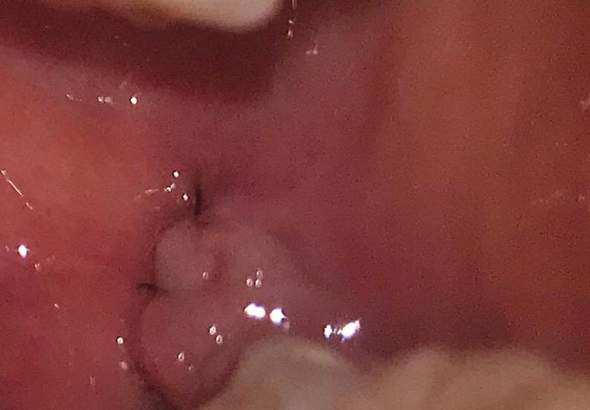

Ein nicht auflösbarer Faden wird einige Tage nach der Operation entfernt werden. Wird einer der vorderen Zähne entnommen so gestaltet sich das Ziehen der Zähne in der Regel einfach da hier nur ein Wurzelkanal gelockert werden muss. In der Regel verwendet man in Deutschland heutzutage OP-Fäden welche siech mit der Zeit unter Wassereinfluss auch Körperflüssigkeiten selbst auflösen.

Muss er da nochmal Aufschneiden. Es sei ein kleines Loch geblieben das man ab und zu mit Wasser spülen sollte und dann spätestens in einem halben Jahr zu gewachsen sein sollte. Langsames Ziehen des Fadens aus der Wunde.

Bei Wundnähten durch Weisheitszahn-Operationen oder anderen chirurgischen Eingriffen kann das Fadenmaterial häufig schon nach einigen Tagen entfernt werden. Sprich der größte Teil des Fadens ist noch im Zahnfleisch. In dieser Zeit bitte keinen Alkohol Kaffee Cola oder schwarzen Tee trinken.

An allen übrigen Körperstellen bleiben die Fäden bis zu drei Wochen an der Wundnaht. Der Zahn lässt sich nicht einfach lösen. Drainage Streifen zum Faden ziehen Weisheit Zahn-op. Bei Wundnähten durch Weisheitszahn-Operationen oder anderen chirurgischen Eingriffen kann das Fadenmaterial häufig schon nach einigen Tagen entfernt werden. Sie müssen es so weit hochziehen dass Sie den Knoten und die darunterliegende Schlaufe sehen können. Wird ein Stückchen vergessen oder übersehen bleibt der Faden unter der Haut stecken und kann Probleme verursachen. Ein nicht auflösbarer Faden wird einige Tage nach der Operation entfernt werden. Muss er da nochmal Aufschneiden. Da stellt sich mir die Frage wie der Zahnarzt nun die Fäden ziehen will.